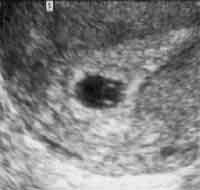

Rond < 8 semaines